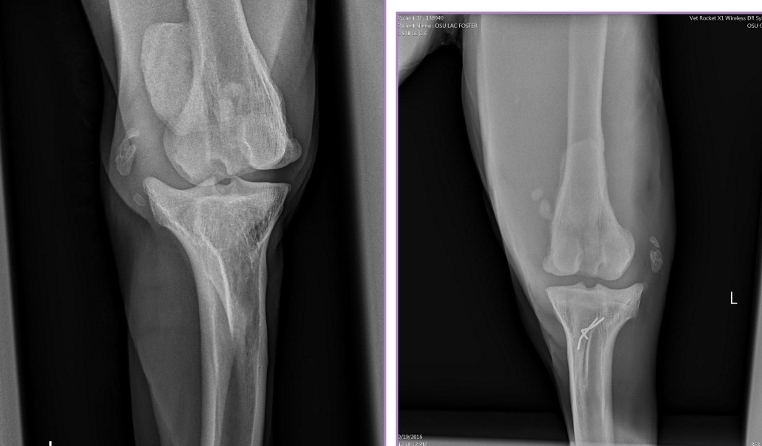

Elbow Dysplasia Clinical Presentation

Medial Compartment and Coronoid Disease

Growing/developmental disease, Bilateral

Et: Growth incongruency radius/ulna, abnormal joint stress, pressure on medial coronoid of ulna

Sig: Large breed dogs, Labs, Bernese Mountain Dog, Male > Female, 6-18 months

Cs: OA, Lameness with ambulation, Decreased ROM of elbow joint, Pain(PE/palpation), Minimal joint effusion, Muscle atrophy

Dt: Lateral, AP, flexed, Crlat-oblique

Rads: Osteophytes(back of elbow), Effusion, Subtrochlear sclerosis, Joint incongruity

CT: Most sensitive